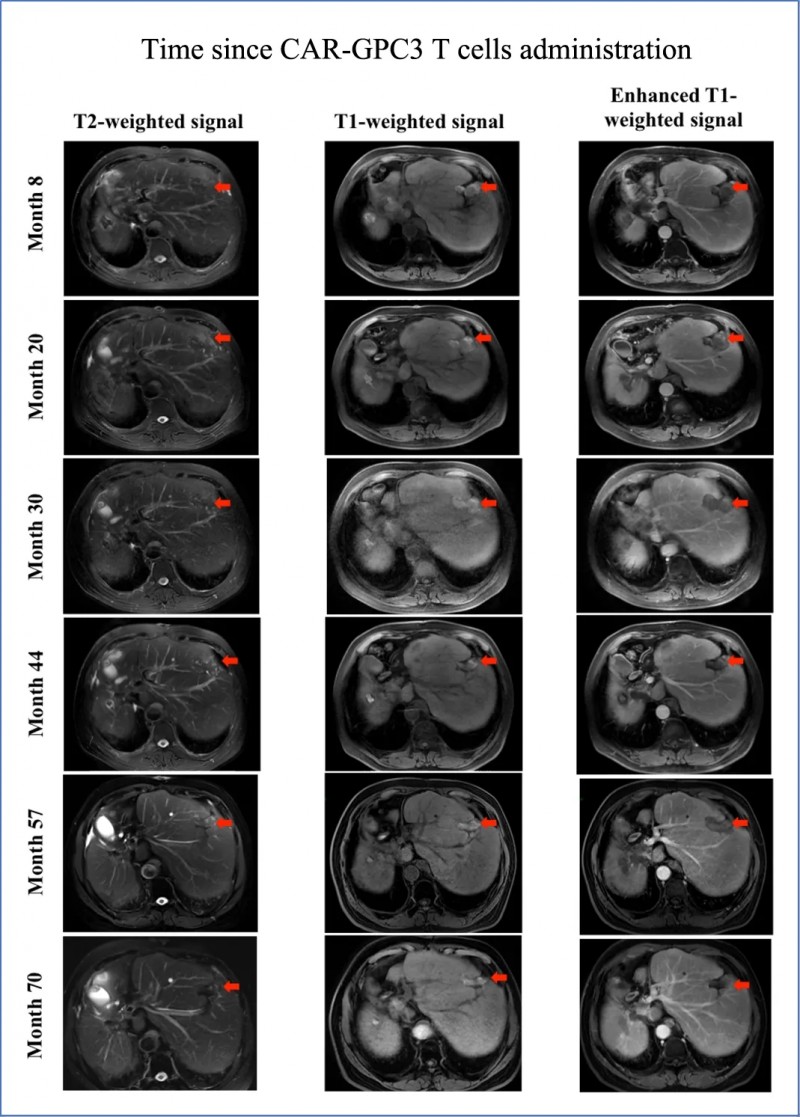

肝癌患者治疗选择有限,整体预后不佳——即使接受手术切除,术后中位总生存期也仅17.8个月。而世界知名期刊《癌症通讯》曾报道一则突破性案例:一名晚期肝细胞癌(HCC)患者,经创新型CAR-GPC3 T细胞疗法治疗后,总生存期超8年,远超肝癌术后17.8个月的中位生存期。

该患者为54岁男性,确诊时为Ib期肝细胞癌(HCC)。他此前已接受过肿瘤切除手术、经导管动脉化疗栓塞术(TACE)、肝癌微波消融治疗(MWA),但病情仍快速进展。MRI检查显示其肝脏存在多灶性病变,且伴随腹膜后淋巴结转移(LM),随后患者入组接受CAR-GPC3T细胞治疗。

此外,CAR-GPC3 T细胞治疗2周后,患者腹膜后淋巴结转移灶(LM)开始缩小,病变短轴直径缩小5.2%、长轴直径缩小4.5%;第7次输注后第7天,靶病变短轴进一步缩小7.4%(详见下图H-I)。后续患者接受伽玛刀放射外科治疗(GKRS)后,AFP水平逐步降至正常范围,且自此进入无癌状态。除2016年7月的GKRS治疗外,患者未再接受任何抗癌治疗,仍保持无病状态超5年,总生存期超8年(详见下图,注:红色箭头表示治疗后的坏死肿瘤)。

▲图源“WILEY Online Library”,版权归原作者所有,如无意中侵犯了知识产权,请联系我们删除